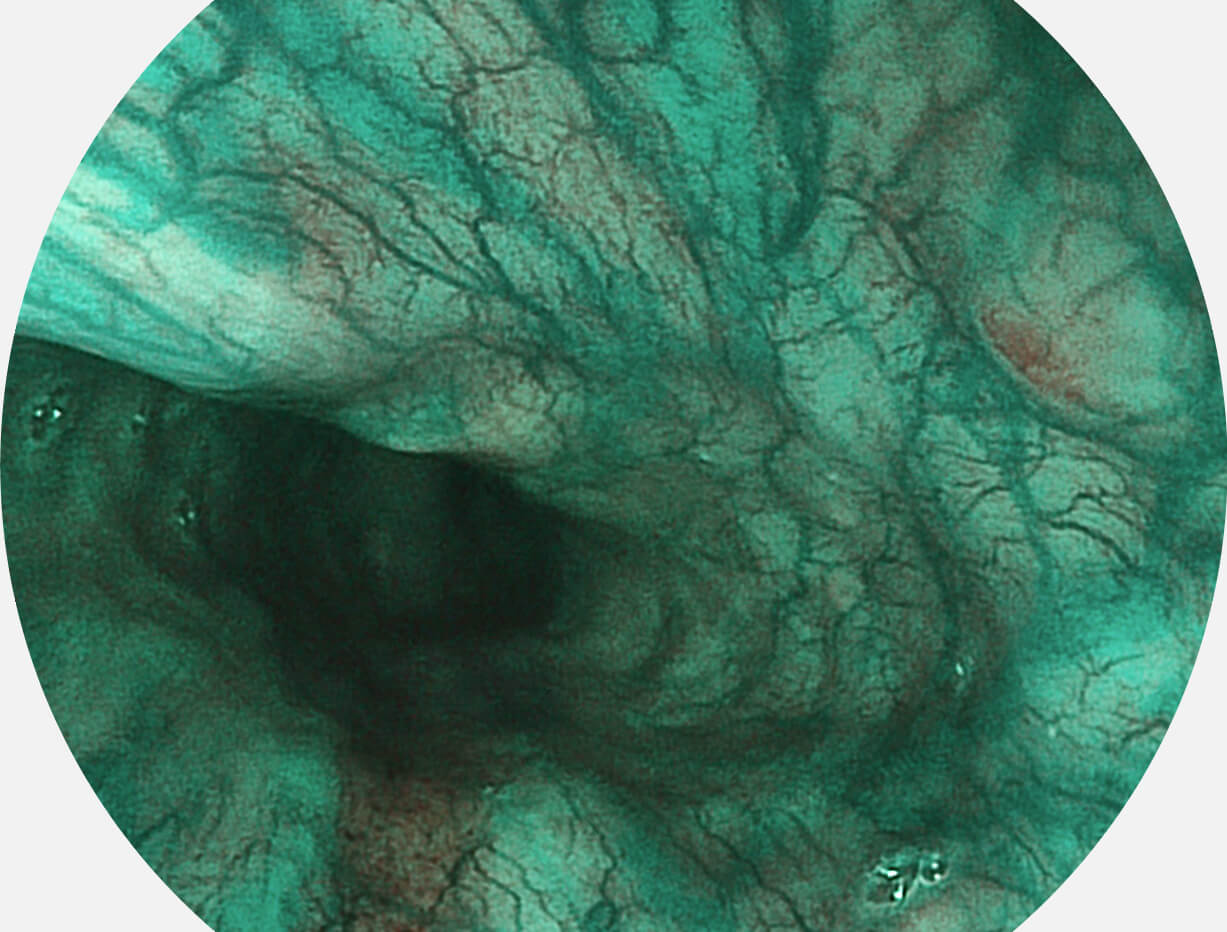

Versatile Intelligent Staining Technology, VIST

强调浅层黏膜结构的同时,保证照明亮度和提升浅层微血管与中层血管颜色对比度,病变边界更清晰。

白光图像

VIST图像